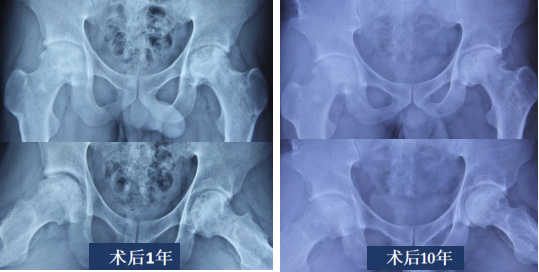

3.外科脱位技术病灶清除打压支撑植骨术

术前X片及MRI见左侧股骨头ARCOⅡ期,JIC C2型,坏死范围大,外侧壁无保留,塌陷风险极高,予行外科脱位病灶清除打压植骨术

术后随访可见左侧股骨头坏死病灶修复良好,股骨头虽有轻度塌陷,但整体形态保持相对稳定